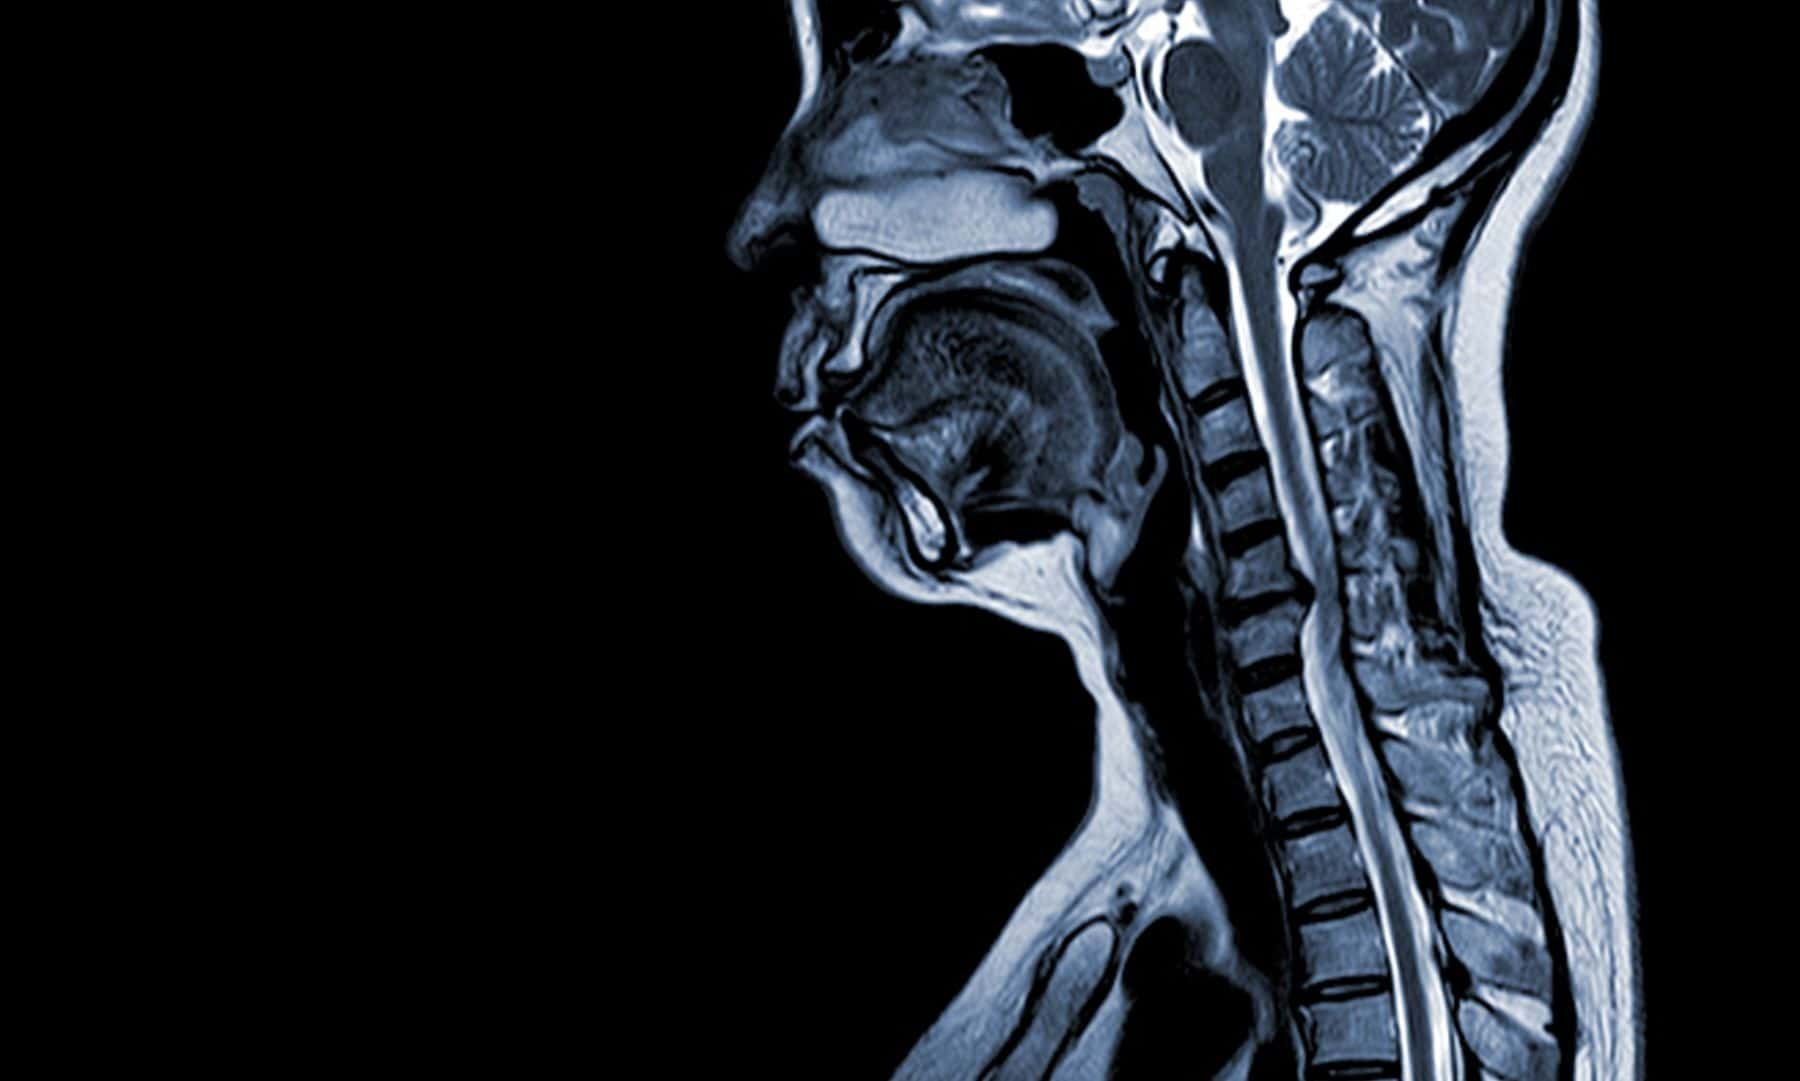

Eventually, after many months of suffering, the patient was diagnosed with cervical myelopathy with severe cord compression in the cervical spine. They underwent multilevel cervical decompression and fusion. This case study examines the PCP’s potential liability in this delayed diagnosis scenario.